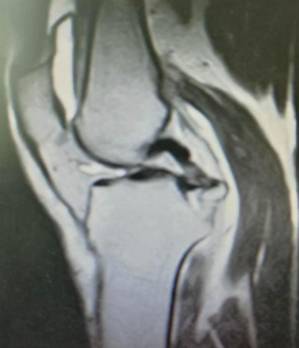

关节镜下肩袖损伤修复术治疗肩袖损伤

优点:损伤小、恢复快。

关节专科

关节专科现有主任医师4名,副主任医师1名,主治医师1名,硕士4名。在股骨头坏死、髋臼发育不良、髋关节骨性关节炎、股骨髋臼撞击综合症、膝关节骨性关节炎、类风湿性关节炎、强直性脊柱炎合并髋关节强直、股骨颈骨折、膝关节运动损伤、肩关节运动损伤、足踝损伤和畸形等骨关节疾病的中西医结合治疗方面独具特色。

手术技术上与国内领先医院接轨,并不断创新。系统开展膝关节骨性关节炎的阶梯治疗方案,早期采用中医中药、理疗、肌力训练等方法;中期采用膝关节周围截骨、单髁置换等手术治疗,充分保留膝关节功能,术后患者康复快。终末期采用膝关节表面置换术治疗。系统开展股骨头无菌性坏死的保头治疗,早期可采用中医中药内服,钻孔减压术治疗,中期可采用髋关节外科脱位技术,充分刮除头内坏死骨,植入新鲜骨质,使坏死股骨头重新获得新生。常规开展复杂的人工髋膝关节置换手术、人工髋膝关节翻修手术。术后采用先进的康复理念和康复方案帮助患者在无痛状态下恢复关节功能。

另外,微创成为我院关节科的一大亮点,膝关节周围截骨术,单髁置换术都是微创手术,患者创伤小,恢复快。我院关节科采用直接前路微创髋关节置换术,切口小,只有8-10cm,顺肌间隙进入,不切断任何肌肉,出血少,无痛,关节脱位率低,术后康复快。关节镜下微创肩袖撕裂修补,冻结肩松解,肩关节撞击症肩峰下减压术,膝关节交叉韧带损伤修补等手术,避免大切口、大创伤、恢复快。